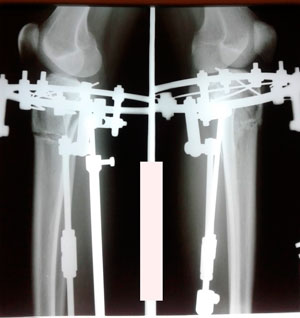

на фиксации

Вложения

IMG_7685-14-12-19-07-41.JPG

IMG_7684-14-12-19-07-41.JPG